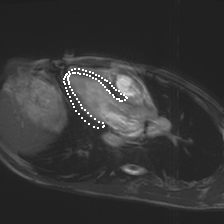

Accurate segmentation and motion estimation of myocardium have always been important in clinic field, which essentially contribute to the downstream diagnosis. However, existing methods cannot always guarantee the shape integrity for myocardium segmentation. In addition, motion estimation requires point correspondence on the myocardium region across different frames. In this paper, we propose a novel end-to-end deep statistic shape model to focus on myocardium segmentation with both shape integrity and boundary correspondence preserving. Specifically, myocardium shapes are represented by a fixed number of points, whose variations are extracted by Principal Component Analysis (PCA). Deep neural network is used to predict the transformation parameters (both affine and deformation), which are then used to warp the mean point cloud to the image domain. Furthermore, a differentiable rendering layer is introduced to incorporate mask supervision into the framework to learn more accurate point clouds. In this way, the proposed method is able to consistently produce anatomically reasonable segmentation mask without post processing. Additionally, the predicted point cloud guarantees boundary correspondence for sequential images, which contributes to the downstream tasks, such as the motion estimation of myocardium. We conduct several experiments to demonstrate the effectiveness of the proposed method on several benchmark datasets.